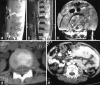

Constitutional mismatch repair deficiency syndrome is a rare autosomal recessive syndrome caused by homozygous mutations in mismatch repair genes. This is characterized by the childhood onset of brain tumors, colorectal cancers, cutaneous manifestations of neurofibromatosis-1 like café au lait spots, hematological malignancies, and occasionally other rare malignancies. Here, we would like to present a family in which the sibling had glioblastoma, and the present case had acute lymphoblastic lymphoma and colorectal cancer. We would like to present this case because of its rarity and would add to literature.